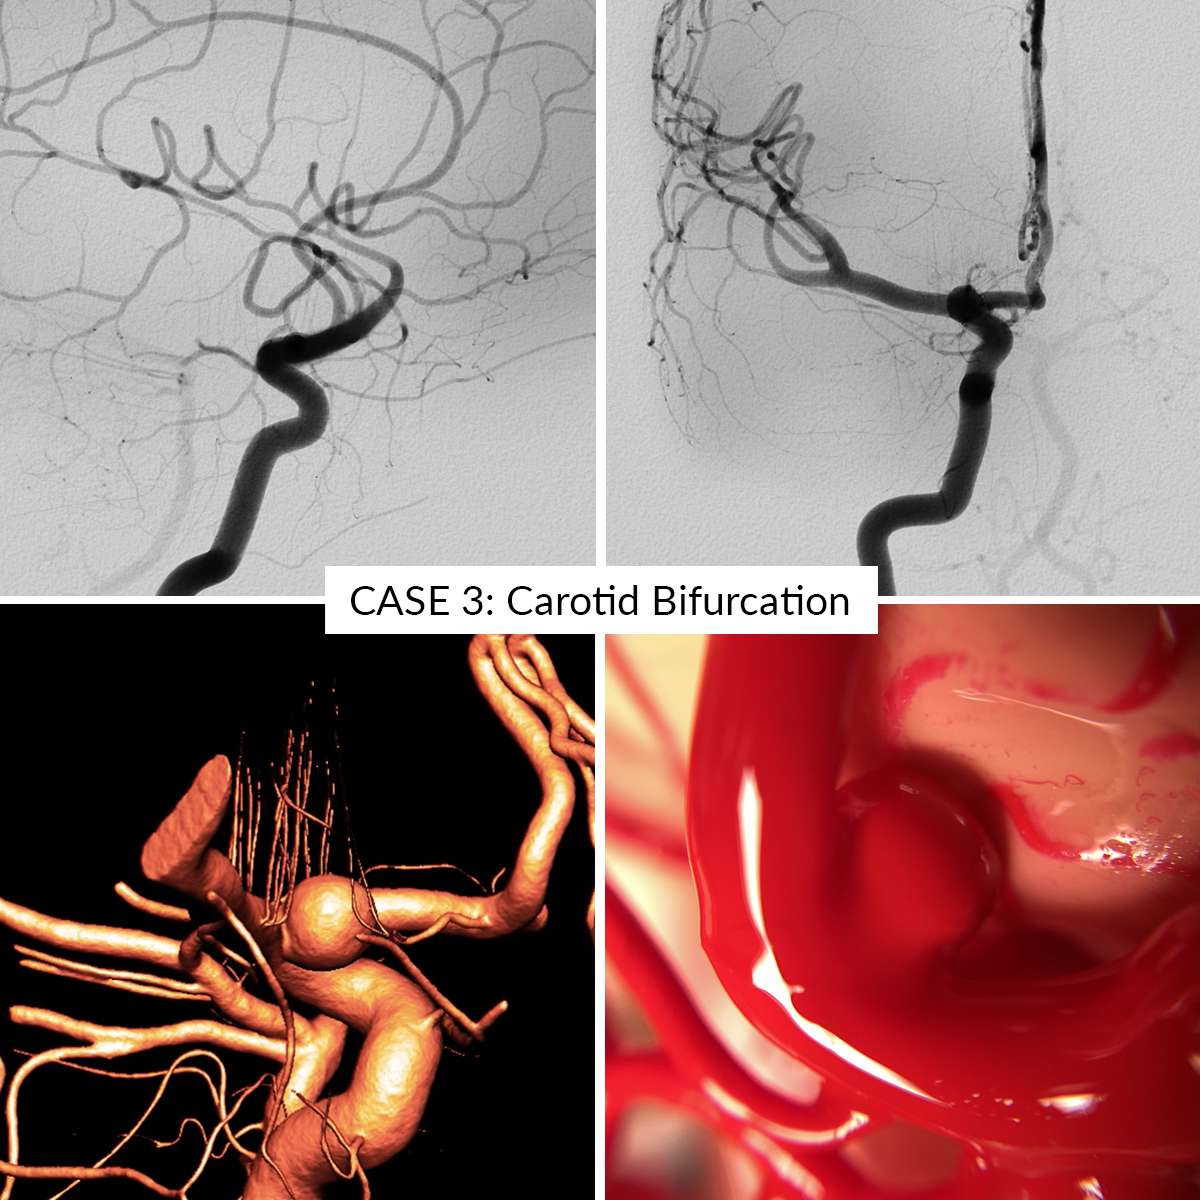

Case 3 : Carotid Bifurcation

In the AneurysmBox simulator you can operate 5 different aneurysm cases:

- Case 3: Carotid Bifurcation

Aneurysms are clippable unlimited number of times. Remove the clips gently to avoid damaging the aneurysms.